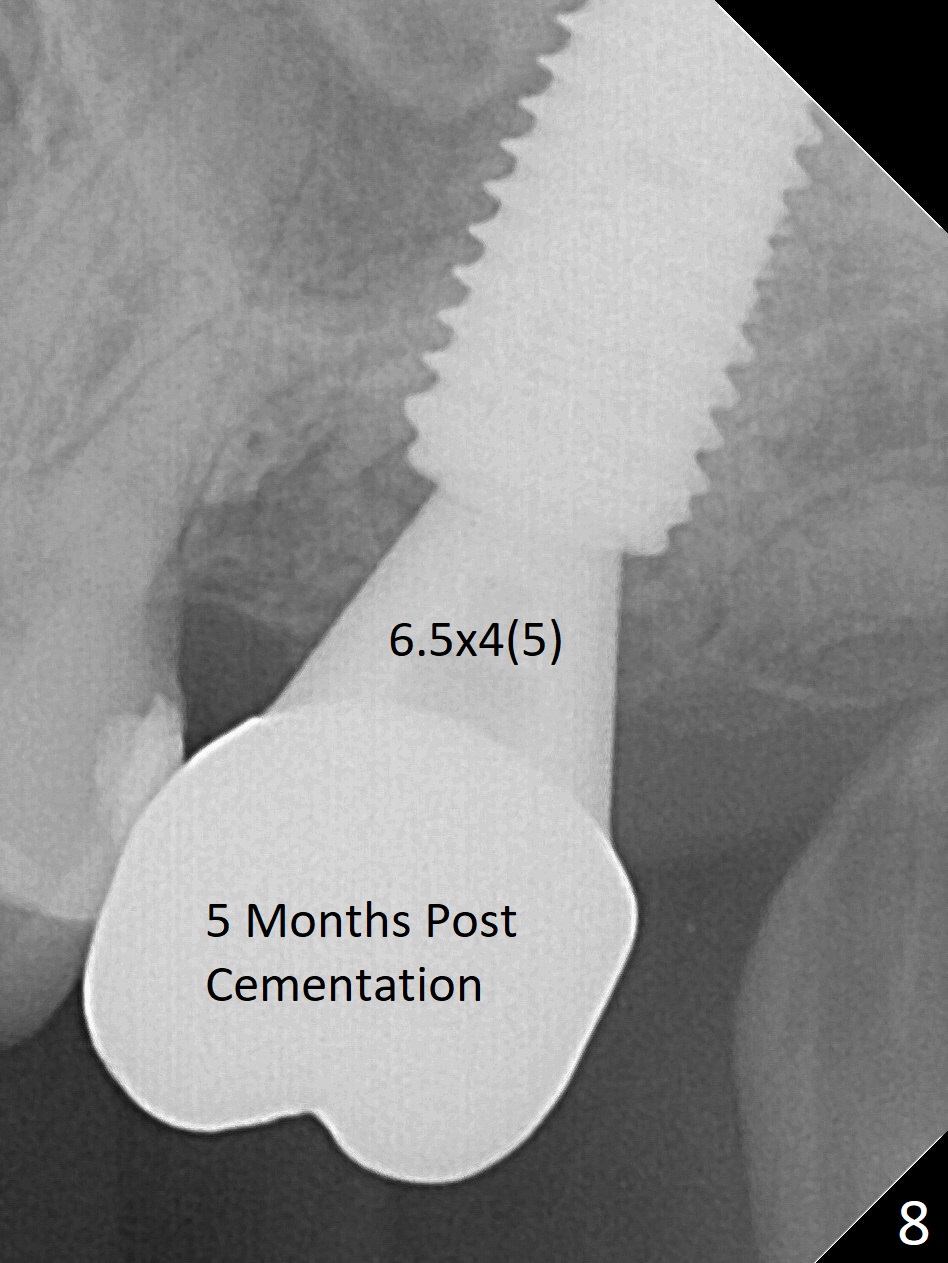

While the tooth #2 has a mesiodistal crack line with symptom (Fig.1 arrowheads, crown pending), the tooth #15 has a mesiodistal fracture (Fig.2). Immediately preop 5x5 cm CBCT (Fig.3) confirms the palatal (P) fracture with palatal bone loss. Although a 5x7.3 mm implant fits the site by design (Fig.4), a much longer implant is required to achieve primary stability past the sinus floor using IBS Magic Expanders (Fig.5,6 (20-30 Ncm; sinus lift with PRF membrane and allograft)). In contrast, primary stability could not be obtained by engaging dummy implant to the socket walls. A short implant without sinus lift is associated with less obvious complication such as fibrointegration. The implant seems osteointegrated 4.5 months postop (Fig.7). The abutment is changed to 6.5x4(5) mm before impression. There is no bone loss 5 months post cementation (Fig.8 (11 months postop)). It is the same 2.5 years post cementation (Fig.9,10).